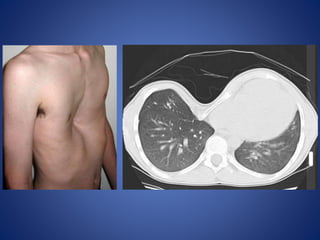

Pectus excavatum

Pectus excavatum (or funnel chest) is a congenital chest wall deformity characterised

by concave depression of the sternum, resulting in cosmetic and radiographic

alterations.

Radiographic features

Plain film

Characteristically demonstrates :

• blurring of right heart border (PA or AP film)

• increased density of the inframedial lung zone

• horizontal posterior ribs

• vertical anterior ribs (heart shaped)

• displacement of heart towards the left

• obliteration of the descending aortic interface

CT

The diagnosis is obvious on CT with the degree of

deformity and mediastinal shift often dramatic.

The Haller index (maximal transverse diameter/

narrowest AP length of chest) is used assess

severity. Normal Haller index is 2.5. Significant

pectus excavatum has an index greater than 3.25.

Pectus excavatum Pectus excavatum(or funnel chest) is a congenital chest wall deformity characterised by concave depression of the sternum, resulting in cosmetic and radiographic alterations.

Radiographic features Plain film Characteristicallydemonstrates : • blurring of right heart border (PA or AP film) • increased density of the inframedial lung zone • horizontal posterior ribs • vertical anterior ribs (heart shaped) • displacement of heart towards the left • obliteration of the descending aortic interface CT The diagnosis is obvious on CT with the degree of deformity and mediastinal shift often dramatic. The Haller index (maximal transverse diameter/ narrowest AP length of chest) is used assess severity. Normal Haller index is 2.5. Significant pectus excavatum has an index greater than 3.25.